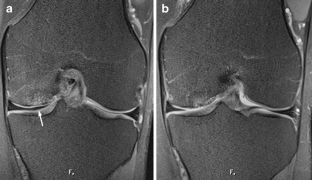

A total of 914 consecutive exams from 875 patients (524 men; mean age, 35 years) were reviewed. Vacuum phenomenon was found in 12 patients (prevalence 1.3%). In six (50%) patients, VP mimicked a meniscal tear, with four cases simulating a torn medial discoid meniscus. The VP signal was not easily differentiated from meniscal signal on most sequences in most cases (9/12). Gradient-recalled echo (GRE) localizer images proved most definitive, with 3D SPACE images the next most effective. Fast spin echo (FSE) images were only occasionally able to differentiate VP from meniscus.

Rarely recognized on MR, VP can mimic meniscal pathology, potentially leading to inappropriate surgery. Because differentiation of VP from the meniscus is challenging on FSE at 3 T, radiologists should become familiar with the appearance of VP and review GRE localizer or 3D images carefully to avoid misinterpretation.